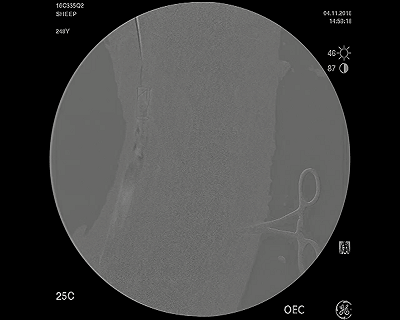

向上的靜脈造影圖,顯示VenoValve的通暢性,允許正常定向的血流返回心臟

下行靜脈造影圖,顯示VenoValve關(guān)閉,防止靜脈血液反流